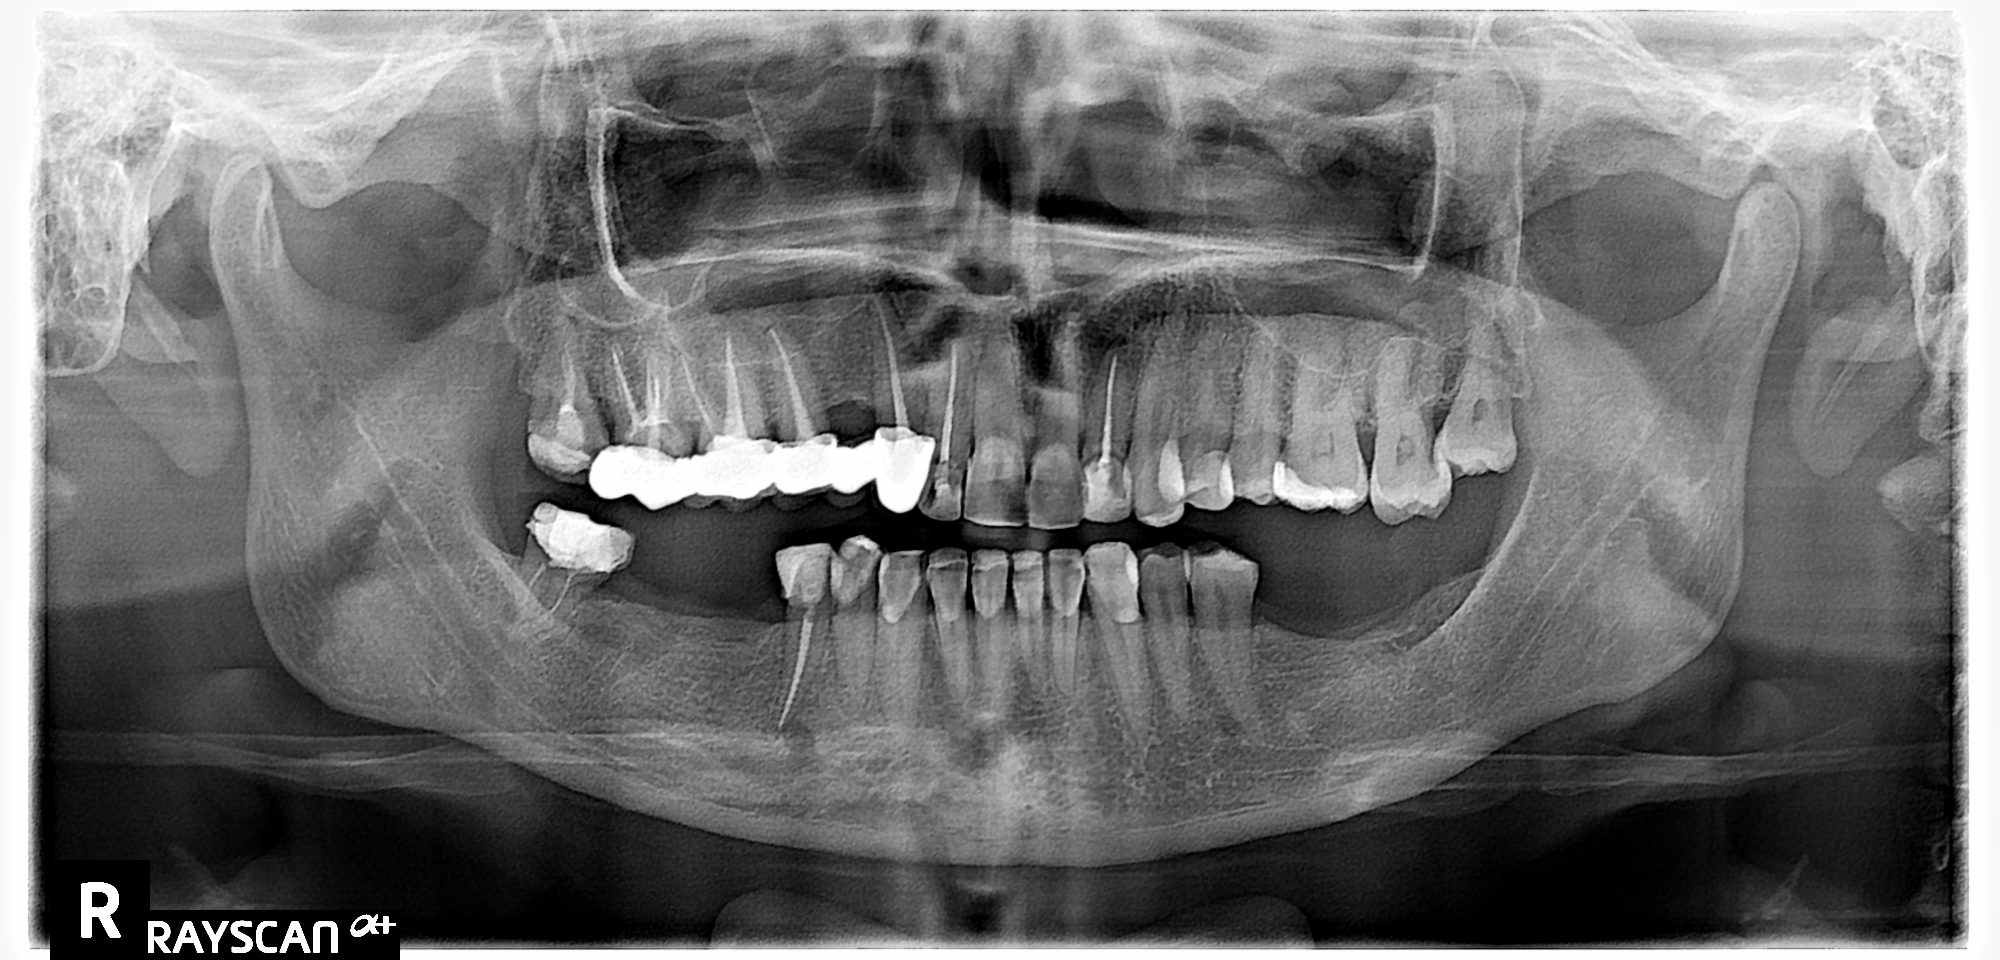

Пациентка обратилась в клинику, т.к. её верхний протез начал шататься.

3Д компьютерное обследование

Пациентка выразила желание заменить существующий металлокерамический мост, установить импланты в области отсутствующих зубов на нижней челюсти и сделать красивую улыбку.